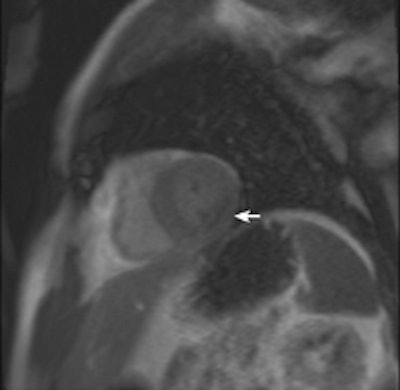

A 64-year-old patient with carotid stenosis. Top left: Coronary CT angiography image. White arrow points to a soft plaque in the midcircumflex artery, with stenosis of the lumen. Calcium score was 64. Top right: Short-axis image of the adenosine perfusion MRI examination. White arrow points to a perfusion defect in the posterolateral wall, during stress. The perfusion defect was not present in the rest series, thus indicating inducible ischemia. Bottom left: Invasive coronary angiography image of the left coronary arteries. Black arrow points to a significant stenosis, corresponding with the location seen on CT. Bottom right: Invasive coronary angiography image after intervention. Good results were achieved after percutaneous coronary intervention with stent placement. All images courtesy of Drs. Rozemarijn Vliegenthart and Martijn den Dekker.Two centers in the Netherlands scanned 115 cardiac-asymptomatic patients age 50 years and older (mean age 65 years; 76% men) with proven aneurismal or stenotic arterial disease with CT, MRI, and sometimes echocardiography as well.